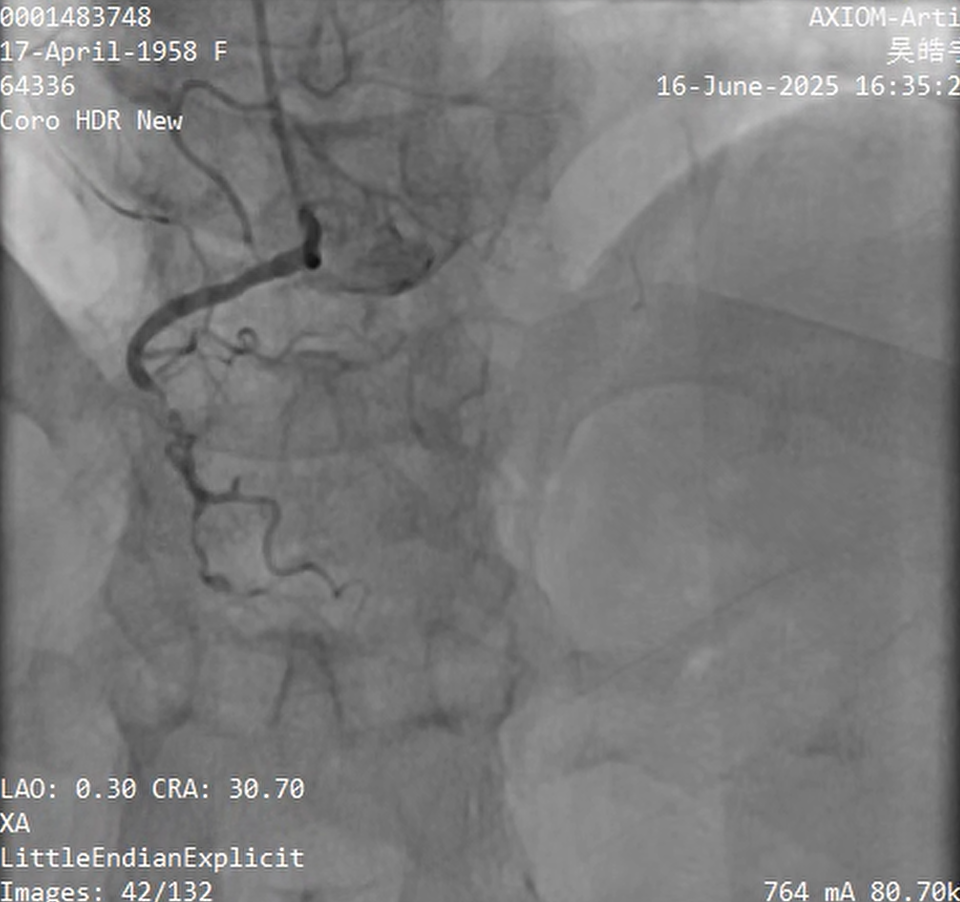

RCA£º

XT-A wire was successfully redirected into the distal true lumen after multiple manipulations;

Advancement of the microcatheter was obstructed by a lesion in the mid RCA;

The microcatheter was withdrawn, and angiography confirmed that the guidewire was in the true lumen;

0.8 ¡¿ 10 mm balloon failed to cross the proximal lesion in the RCA2;

With the support of a Guidezilla catheter, the 0.8 ¡¿ 10 mm balloon successfully crossed the lesion;

Under IVUS guidance, a 2.0 ¡¿ 38 mm DCB was implanted in RCA2-3, 3.0 ¡¿ 32 mm and 3.0 ¡¿ 19 mm DES were implanted in RCA1-2;